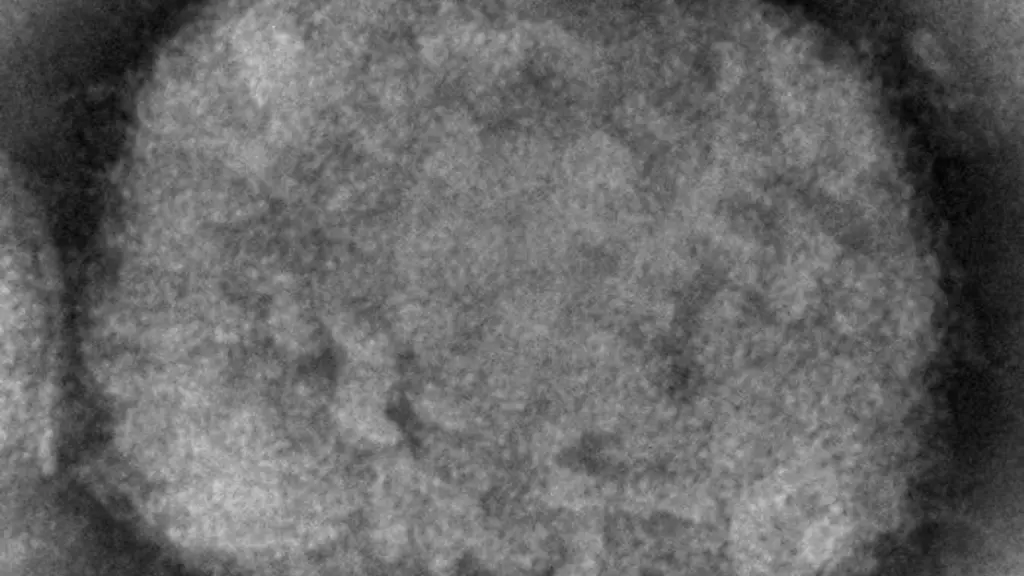

Mecklenburg-VorpommernErster Affenpocken-Fall für Mecklenburg-Vorpommern gemeldet

Neubrandenburg (dpa/mv) - Für Mecklenburg-Vorpommern ist ein erster Affenpocken-Fall gemeldet worden. Es handele sich dabei um eine in Berlin festgestellte Infektion bei einem im Nordosten gemeldeten Mann, sagte am Donnerstag Anja Neutzling, Sprecherin des Landesamtes für Gesundheit und Soziales (Lagus). Zuvor hatte die "Ostsee-Zeitung" berichtet.

Der Mann ist demnach im Landkreis Mecklenburgische Seenplatte gemeldet, er habe sich vermutlich in Berlin bei einem anderen Menschen angesteckt. Der Fall sei am 24. Juni von dort gemeldet worden. Entscheidend für die Zuordnung der Fälle ist der Ort des ersten Wohnsitzes. Das Robert Koch-Institut (RKI) gab die Zahl der Affenpocken-Fälle in Deutschland zuletzt mit rund 970 an. Berlin ist besonders betroffen.